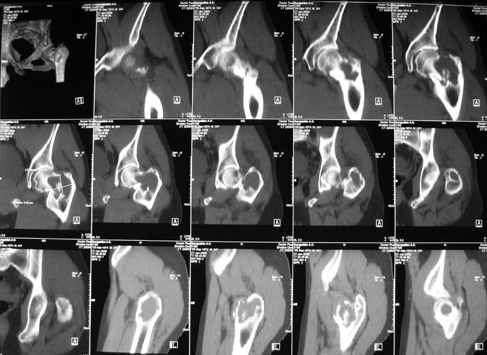

Уважаемые коллеги! Больной (1974 г.р.) травма 26.01.2009г., у пал на ра-боте с высоты своего роста, доставлен в одну из горбольниц Екатеринбурга в травматологическое отделение. На рентгенограмме выявлен патологический перелом чрезвертельной области левого бедра.

Доброкачественная опухоль (ОБК?, энхондрома?), по данным RS. Дополнительно произведено КТ. Наложено скелетное вытяжение.

Прилагаются: рентгенограмма и данные СТ